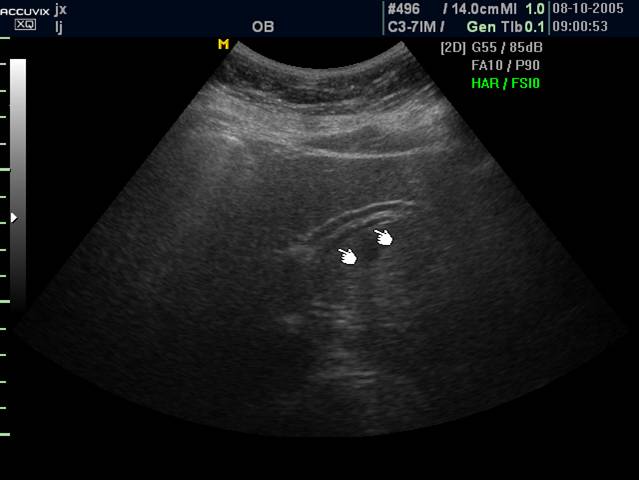

4 胆道蛔虫病